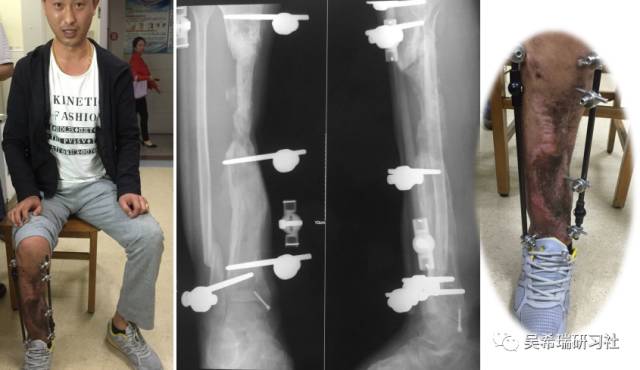

病例7

小腿骨折继发感染骨髓炎反复皮瓣9个月未下地骨质疏松继发肥胖

TIPS:9个月反复皮瓣未下地骨质严重疏松病灶清除后应用表面羟基磷灰石涂层骨圆钉半开放植骨 + 骨搬移骨水泥设计为自行吐出伤口开放换药走路骨质改善、骨愈合治疗足下垂